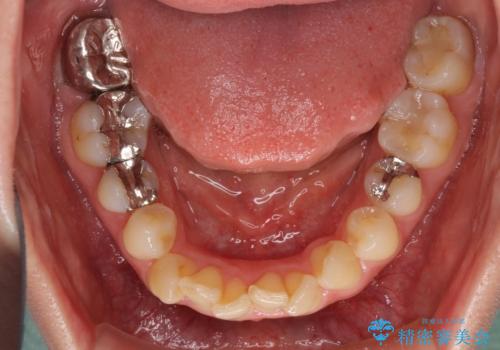

- 上下の前歯のデコボコを治したいとのことで来院された患者様です。

上下顎ともにIPR(歯と歯の間を削る)と歯列全体の拡大によって叢生が解消するように設計し、インビザラインにより治療を行うこととしました。